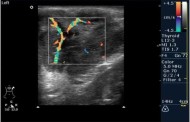

Определить наличие олигогидрамниона может только врач при помощи УЗИ. При этом важно не только подтвердить диагноз, но и оценить степень недостатка амниотической жидкости. Врач может определить объём жидкости и, исходя из полученных данных, сделать выводы о состоянии плода и материнском здоровье.

- Ультразвуковое исследование (УЗИ) — основной метод диагностики.

- Объём амниотической жидкости обычно измеряется в см по четырем основным карманам.